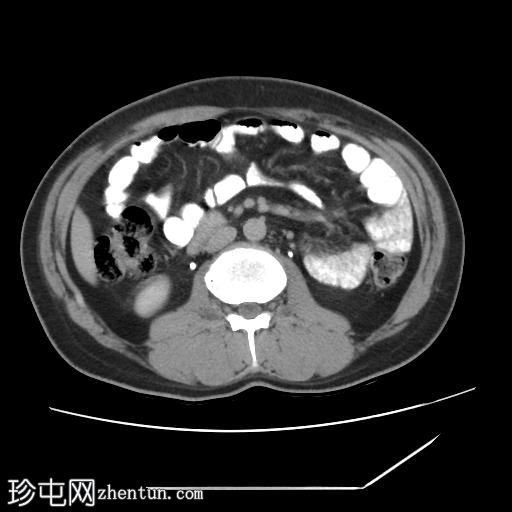

冠状位增强扫描(口服造影剂)

CT扫描显示胰腺组织完全包绕十二指肠第二段。未发现胰周结节或肿块。

环状胰腺是一种形态学异常,其特征是胰腺组织完全或部分环绕十二指肠第二段。这种情况可导致十二指肠梗阻,因此放射科医生识别此病至关重要,因为他们通常是第一个提出诊断的医生。